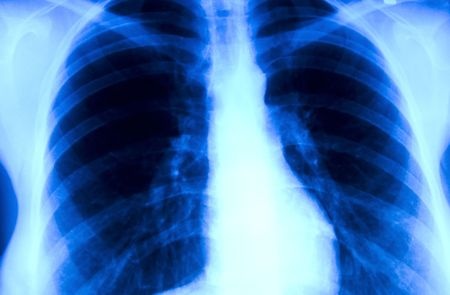

Naukowcy z Florydy zidentyfikowali nowy biomarker, który wiąże się z lepszym rokowaniem pacjentów z nowotworami okolic głowy i szyi oraz rakiem niedrobnokomórkowym płuc. Wyniki ich pracy mogą przyczynić się do rozwoju nowych metod diagnostycznych i lepszego planowania terapii pacjentów onkologicznych.

Zespół kierowany przez naukowców z The Scripps Research Institute (TSRI) na Florydzie dokonał bardzo ciekawego odkrycia. Naukowcom udało się zidentyfikować biomarker, który wiąże się z lepszym rokowaniem pacjentów z nowotworami głowy, szyi oraz płuc. Szczegóły ich pracy można znaleźć na stronach internetowych magazynu Cancer. Białko CCT-alfa jest "antygenem", który stymuluje układ odpornościowy do wytwarzania przeciwciał przeciwko niemu.

Białko ERCC1 bierze udział w naprawie DNA, natomiast CCT-alfa zaangażowane jest w syntezę błon komórkowych i przekaźnictwo komórkowe związane z błonami. Wyniki pracy amerykańskiego zespołu są oparte na analizie próbek 187 pacjentów z rakiem niedrobnokomórkowym płuca oraz 60 osób z nowotworami kolczystokomórkowymi głowy i szyi. Po analizie okazało się, że ekspresja CCT-alfa była związana z lepszym odsetkami przeżywalności. Co ważne, dłuższe przeżycie obserwowano także u pacjentów z rakiem niedrobnokomórkowym płuca leczonym tylko operacyjnie - bez użycia chemioterapii opartej na pochodnych platynowych.